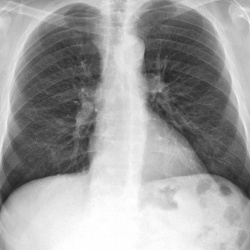

Добрый день. Подскажите пожалуйста, в верхних отделах правого легкого линейная тень. что это может быть : фиброзные изменения или дисковидный ателектаз. ? Спасибо